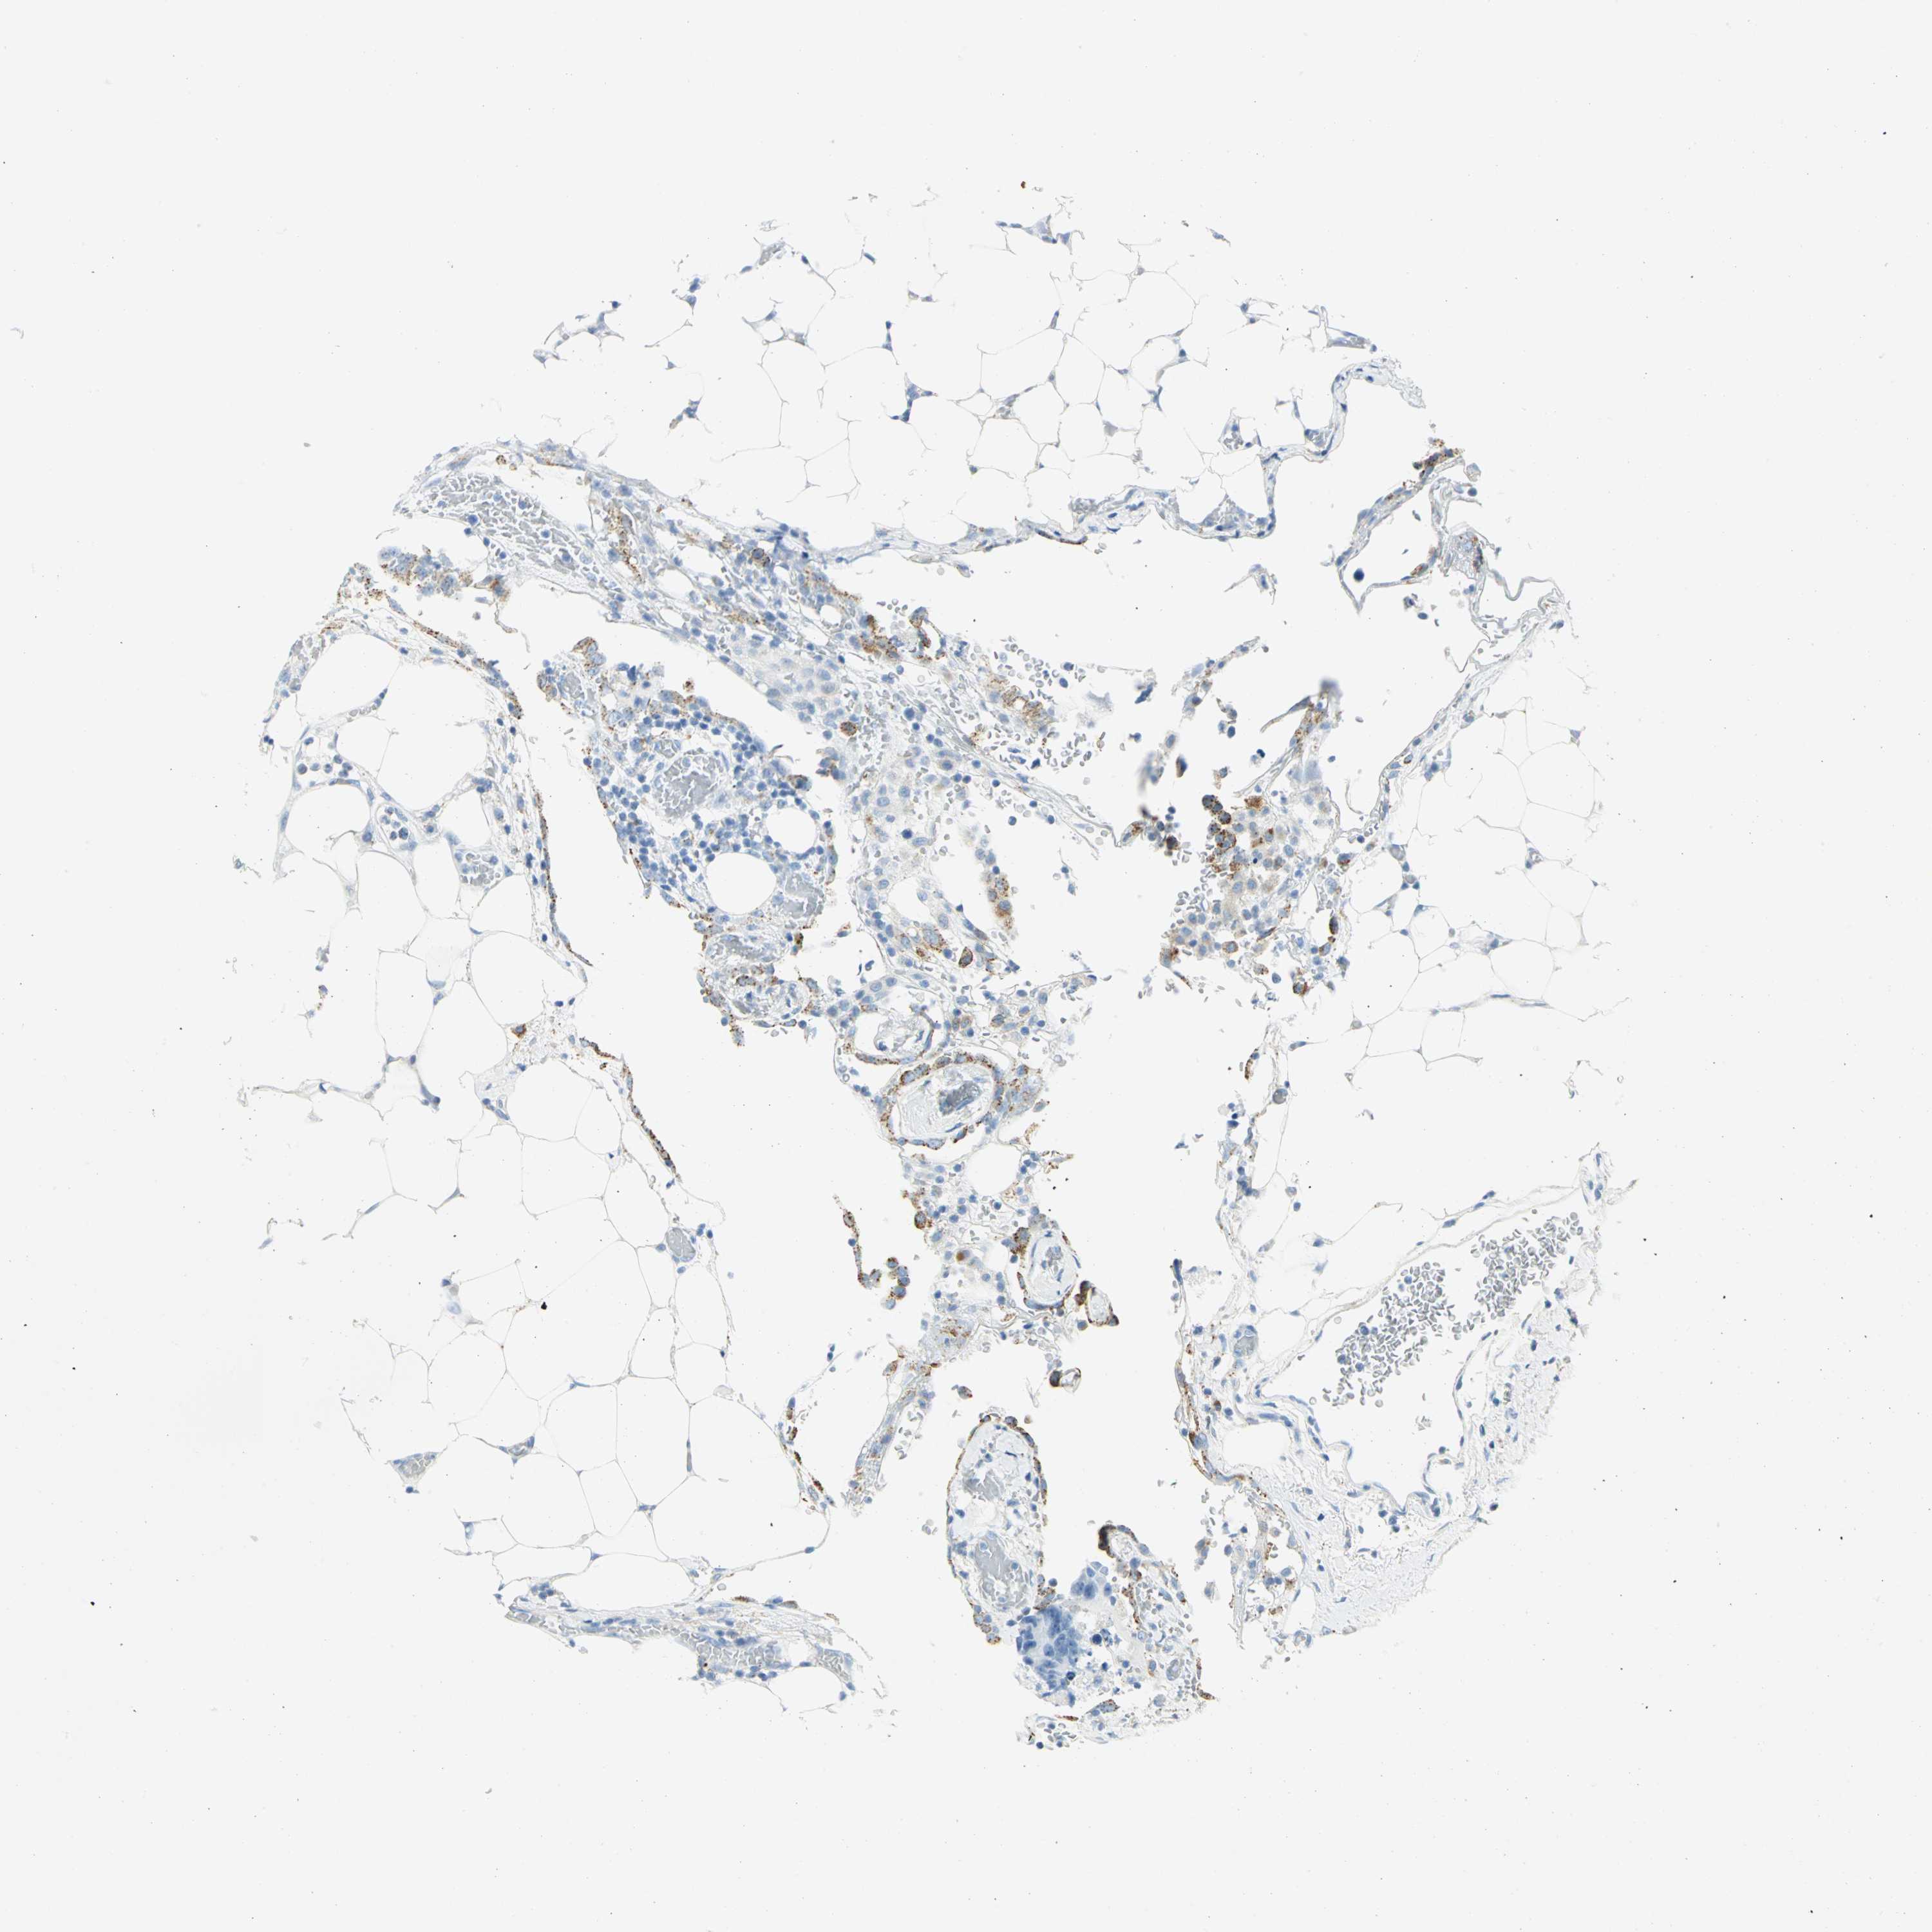

CANCER COLORECTAL CANCER Show tissue menu

Colorectal cancer

Human cancer

Colon adenocarcinoma